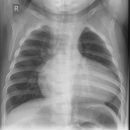

Thorax im Hängen

Qualitätskriterien

Abgebildet müssen sein: beide Lungenflügel, PC-Winkel und Lungenspitzen. Die ersten 3-5 Rippen sollten schwach erkennbar sein, die inneren Scapularänder sollten außerhalb des Thorax liegen.